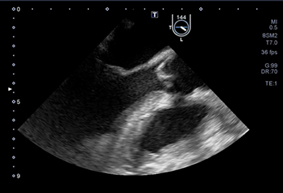

圖一、TEE可觀查主動脈瓣是否壓迫及清晰的心臟影像

經食道超音波(Transesophageal Echocardiography, TEE)是一種高清晰的心臟影像技術,已在許多急診和重症醫學領域中發揮了重要作用。與經胸超音波(Transthoracic Echocardiography, TTE)相比,TEE具有更高的影像解析度,特別適合在CPR過程中使用。TEE是利用超音波探頭經由食道接近心臟,由於食道與心臟間無任何干擾組織,易獲取高解析度的心臟結構影像,尤其在CPR進行時,可以不受胸壁壓胸的干擾,可連續監測心臟活動和血液動態。

* 精準定位壓胸位置:研究表明,按壓位置對ROSC有顯著影響。TEE可以清楚地顯示心臟瓣膜和主要血管的情況,幫助急救人員避免壓迫主動脈瓣,從而提高急救的成功率。